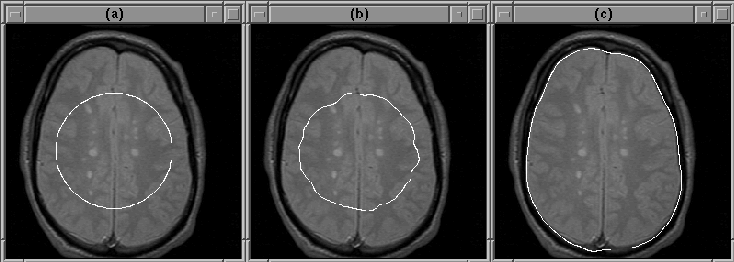

The balloon force contributes significantly to the accurate convergence of the active contour model algorithm when the initial guess is far from the object boundary. Figure 5.13 illustrates this contribution.

Figure 5.13: The balloon force enables the active contour model algorithm to find the intracranial boundary when the initial guess is poor. (a) Initial guess. (b) Final contour with balloon force disabled. (c) Final contour using balloon force.

Given an initial contour well inside the brain, the active contour model algorithm easily finds the intracranial boundary using balloon force. When the balloon force is disabled, the final contour attaches itself to detail inside the brain.